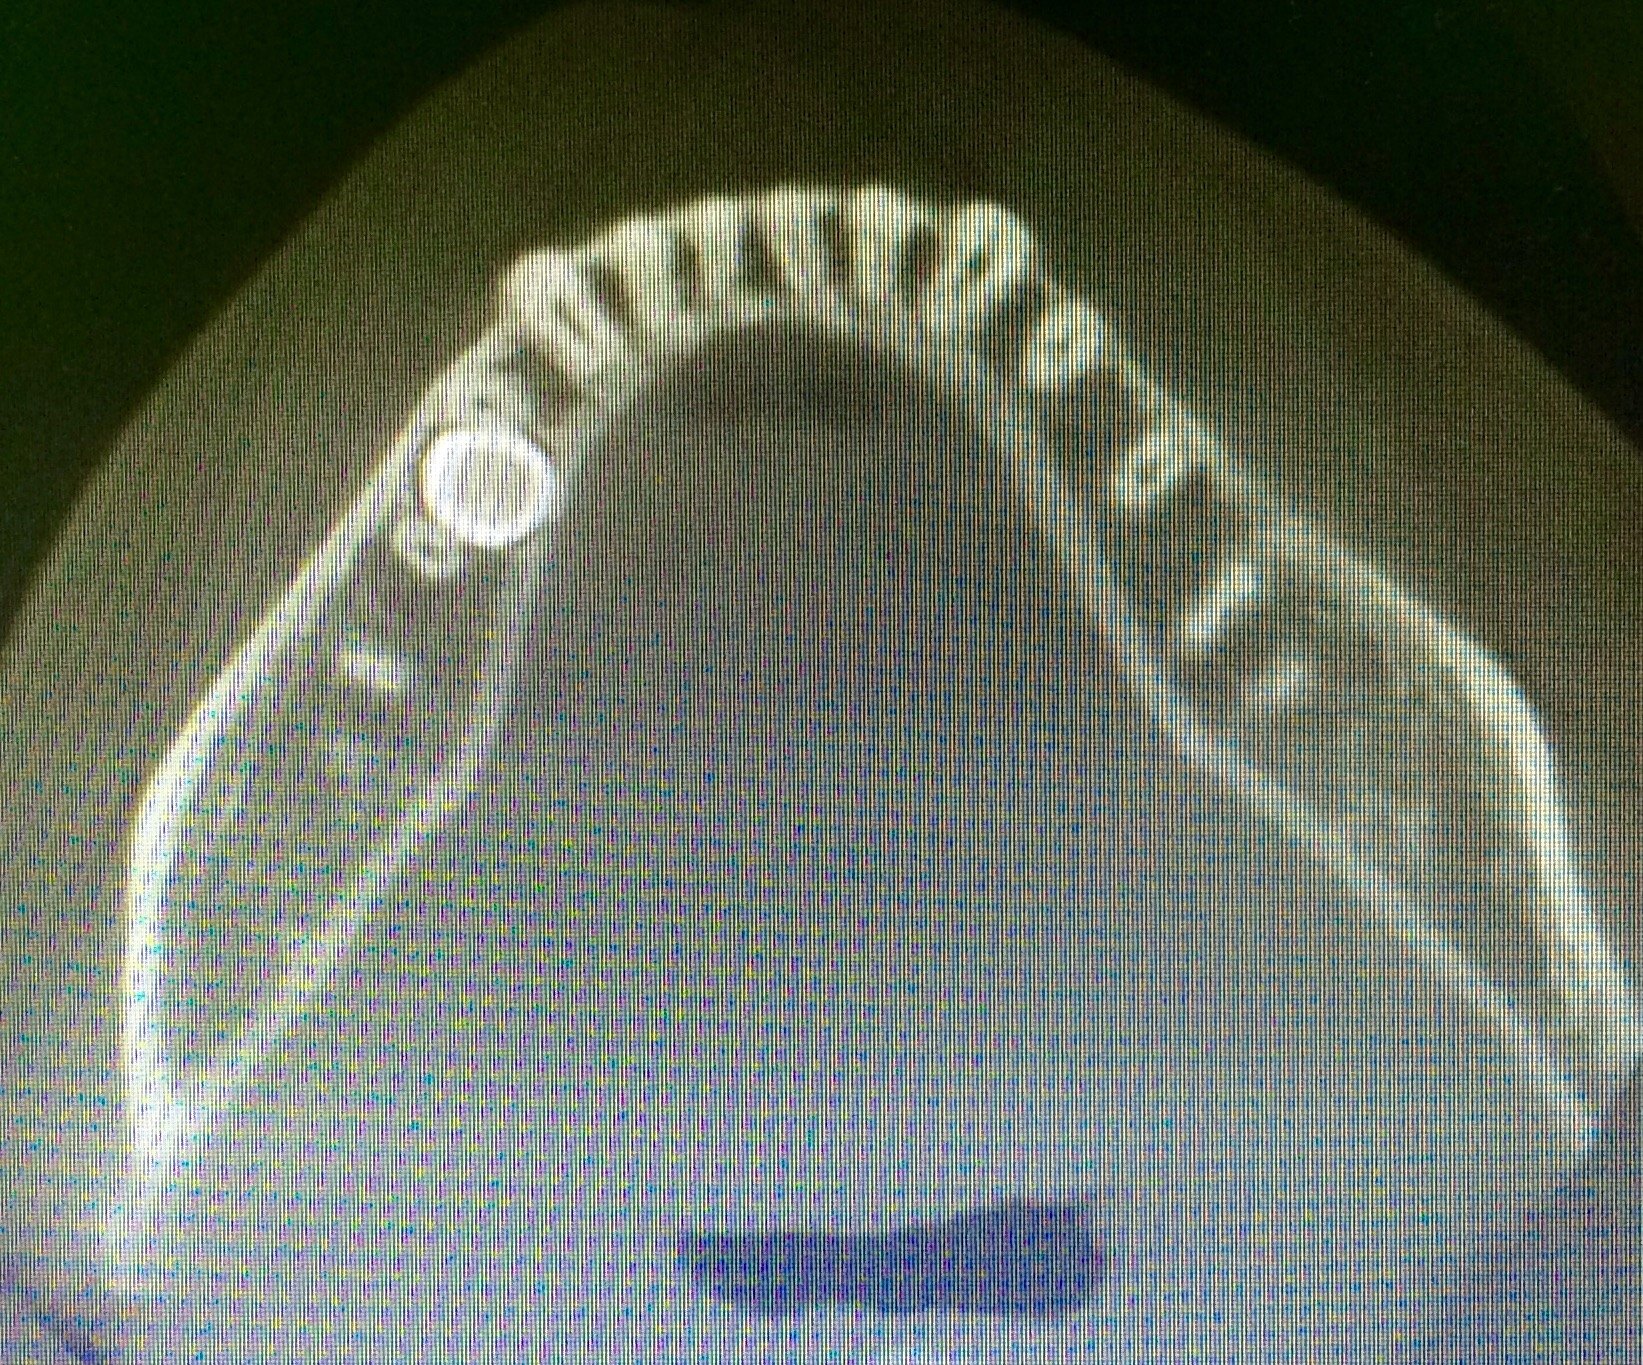

双侧上尖牙开窗牵引

图片尺寸3616x2410